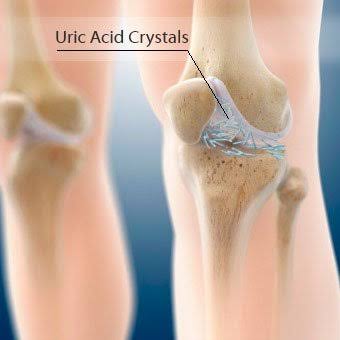

痛风性关节炎是由于尿酸盐结晶沉积在关节内的软骨、骨髓、关节囊以及其他结构当中诱发的炎症。大家看下图所示的切片,就会明白痛风性关节炎有多可怕,在患者的骨髓当中都可以看到痛风石的形成。

痛风性关节炎的急性期会有非常明显的关节红肿热痛,这种疼痛多数在后半夜发作,容易在受凉之后发作。患者表现出来不仅是活动以后的疼痛,而且不动也会很痛。如果患者有过高尿酸血症的病史,或者是有过痛风发作史,那么可就可以做出非常明确的诊断。

当痛风性关节炎进入慢性期的时候,往往是比较危险的时候,虽然这个时候患者没有任何的症状,但是这些痛风石会逐渐慢慢的沉积在患者的关节内,虽然并不会引起患者的疼痛,但是随着时间的累积,尿酸盐沉积的增多会严重导致患者的关节变形,影响患者的关节功能。此时往往给予患者进行普通的x光检查,或者从体表就能发现患者是存在明确的痛风性关节炎呢。